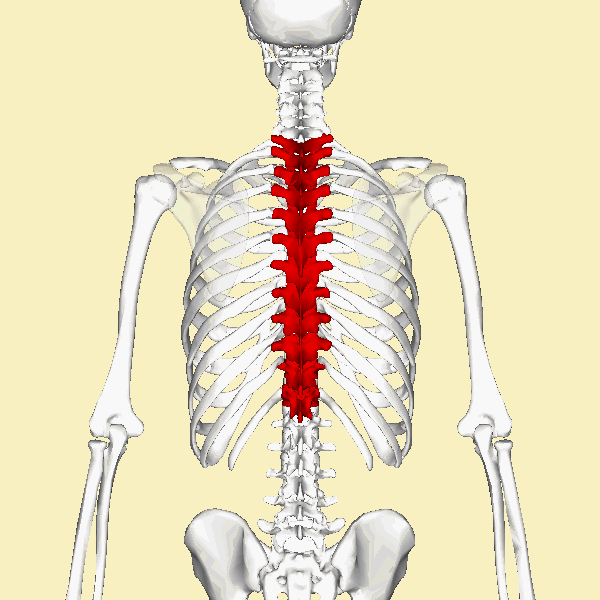

흉추(thoracic vertebra)

경추(목뼈)와 요추(허리뼈) 사이에 위치하여 척주의 중간 부위. 12개의 추골(T1-T12)로 이루어져있으며 아래쪽으로 갈수록 크기가 증가한다.

https://en.wikipedia.org/wiki/Thoracic_vertebrae